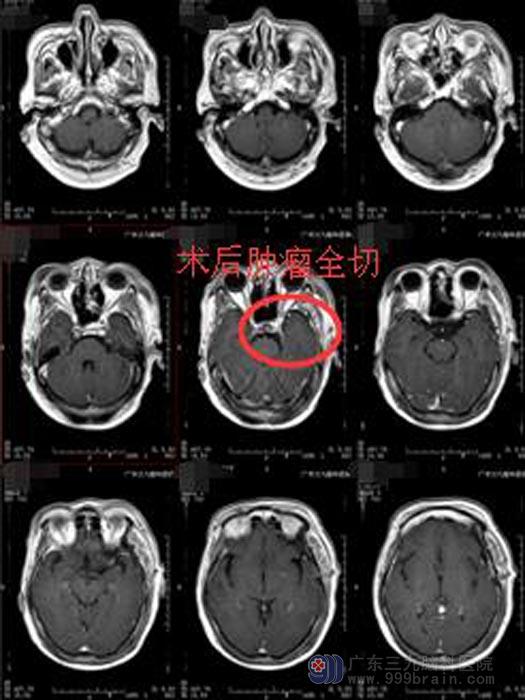

完善相关的术前准备后,由鲁明副院长主刀在全麻下行左侧蝶骨脊脑膜瘤切除术。术中见肿瘤有完整的包膜,质韧,血管丰富,周围粘连重要脑组织,部分包绕左侧颈内动脉、视神经等。显微镜下细心分离与脑组织粘连的肿瘤,边分离边分块切除,颈内动脉、大脑中动脉以及视神经、动眼神经均保护完好,肿瘤切除完整。术后,章姨神志清醒,活动良好,头晕视物模糊症状得到明显的改善。